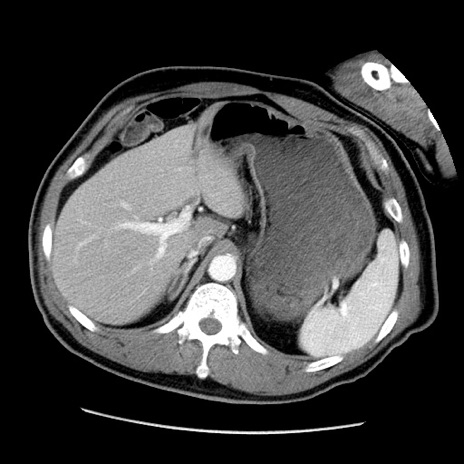

症例22(横断像)

【症例】50歳代男性

【主訴】腹痛

【現病歴】AVMからの被殻出血のため回復期リハ病棟入院中。 本日午後3時頃急に下腹部痛が出現した。

【既往歴】AVM、被殻出血、虫垂炎、高血圧

【身体所見】意識晴明、左半身不全麻痺、会話の理解は良好、36.5°C、腹部:膨隆、全体に板状硬、下腹部正中に圧痛点あり、反跳痛-、筋性防御不明、右下腹部にope scar

【データ】WBC 9400、CRP 0.06